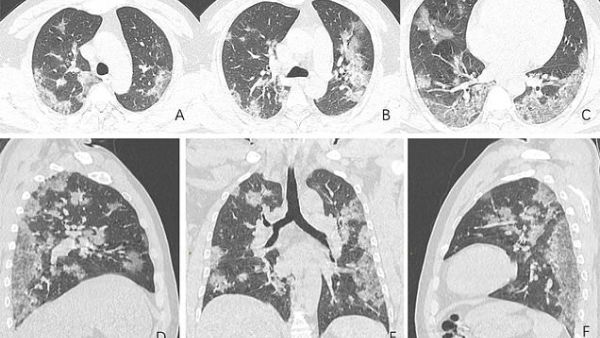

The scans, released by the Radiological Society of North America, show how the fluid in the spaces of the man's lungs became more pronounced over time, as evident when comparing image A to image F.

The man was admitted to hospital on December 25, 2019 after suffering from a fever and cough for almost two weeks. Doctors diagnosed the man with pneumonia and acute respiratory distress syndrome.

Despite being treated by doctors, he died a week later.